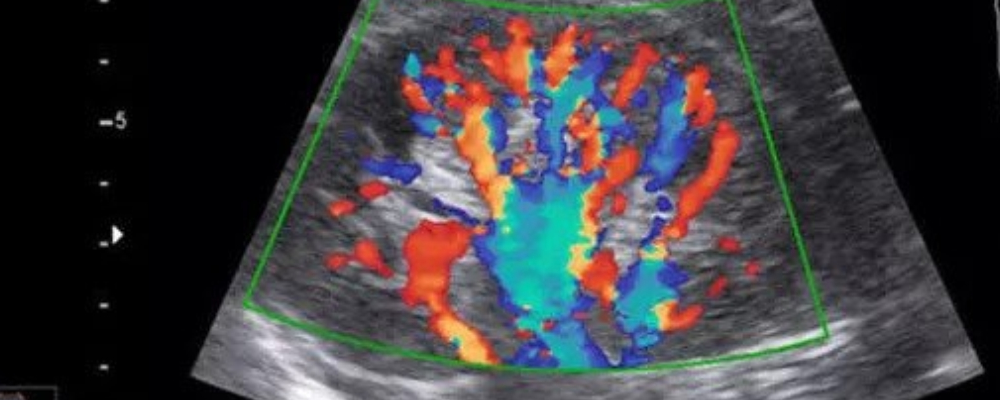

- Color Doppler-: This type of Doppler uses a computer to change sound waves into different colors. These colors show the speed and direction of blood flow in real time.